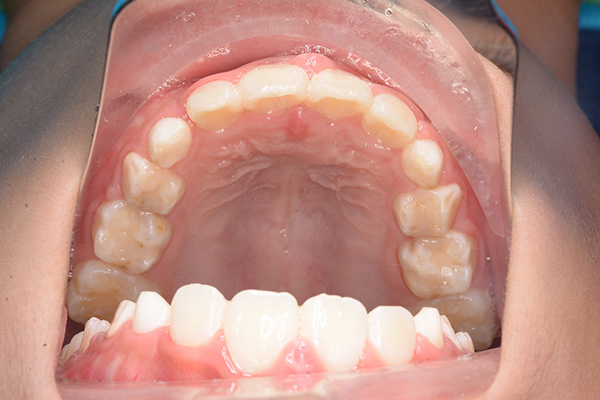

| 主訴 | 上顎前歯のでこぼこ | 診断名 | アングルⅡ級叢生症例 | ||||

| 既往歴として上顎正中過剰歯(2本)は抜去済み。その影響で上顎右側中切歯は捻転して萌出しており、下顎右側中切歯と早期接触が認められたため2x4(上顎のみブラケット装着)にて前歯部の改善を行った。現在は永久歯列完成まで経過観察を行い、希望があれば口元の突出感を改善するために本格矯正治療を行うことにしている。 | |

| 批評・予后 | 早期治療によって前歯部の咬合干渉は回避され、その後の永久歯への交換は順調である。 |